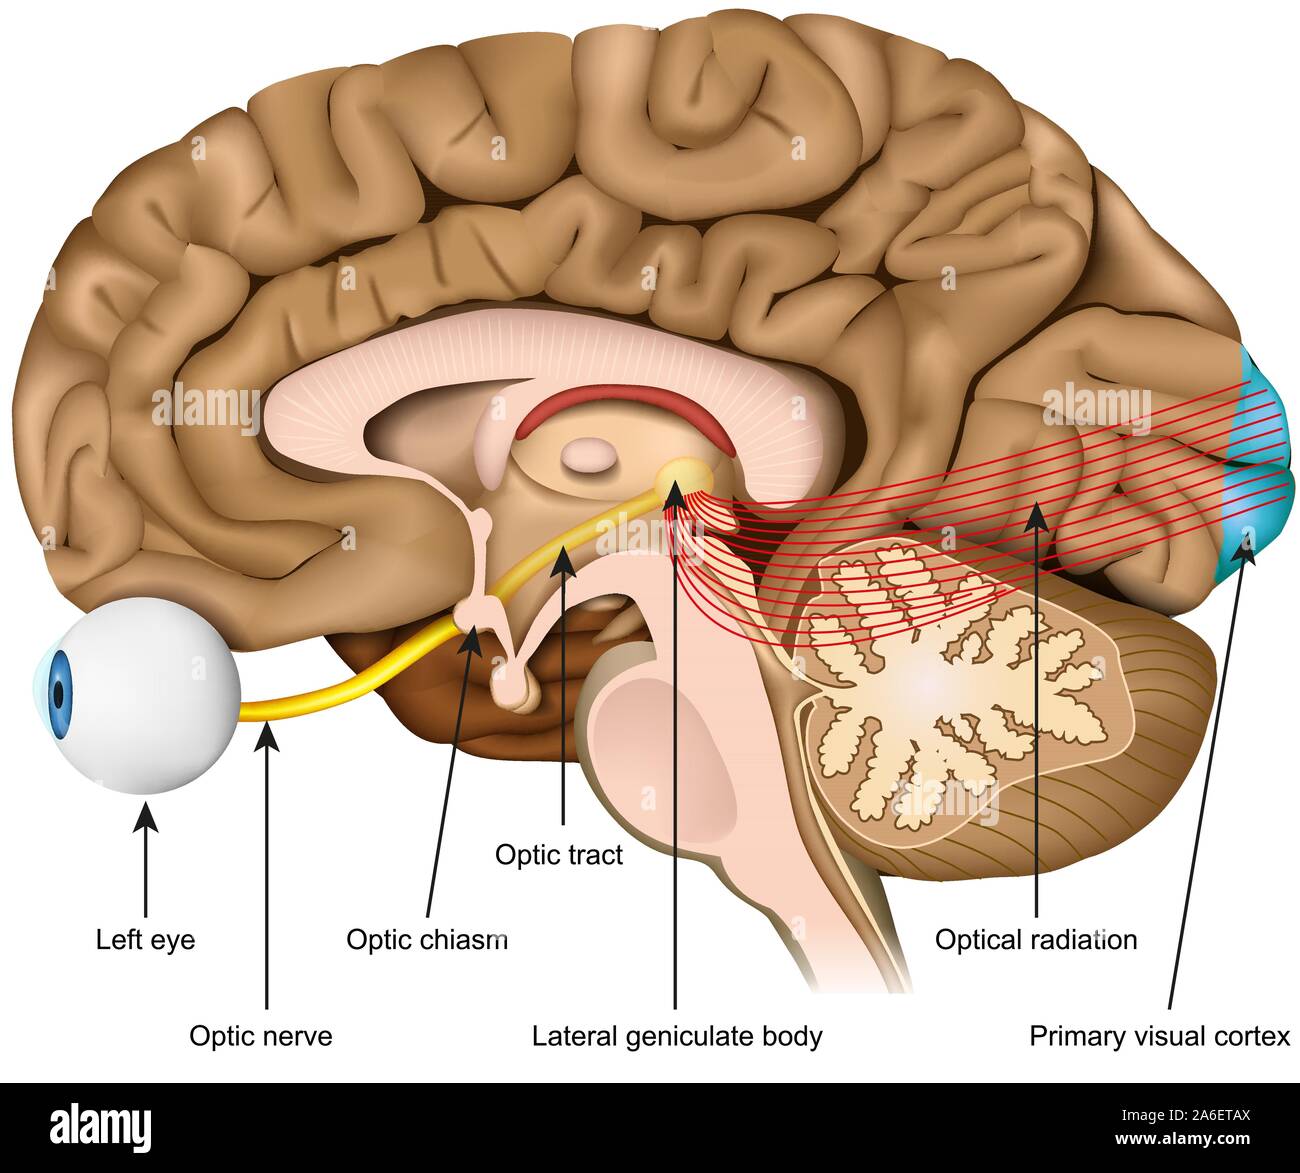

RF2PPWR9E–Cervello umano con parte del sistema limbico e corteccia cerebrale, nucleo suprachiasmatico, chiasmo ottico, Ipotalamo, E Pineal Gland